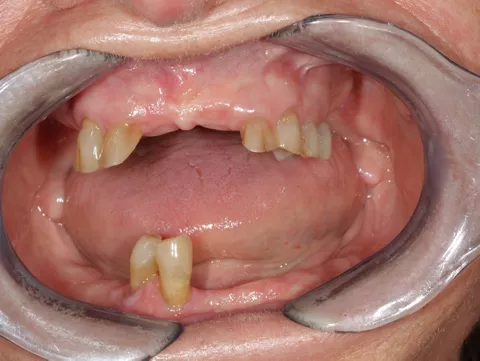

2. Display of teeth once pretreatment was completed. Treatment plan for the implant positions done using CBCT and intraoral scans at this stage.

16. Display of the finished lower jaw work after osseointegration.